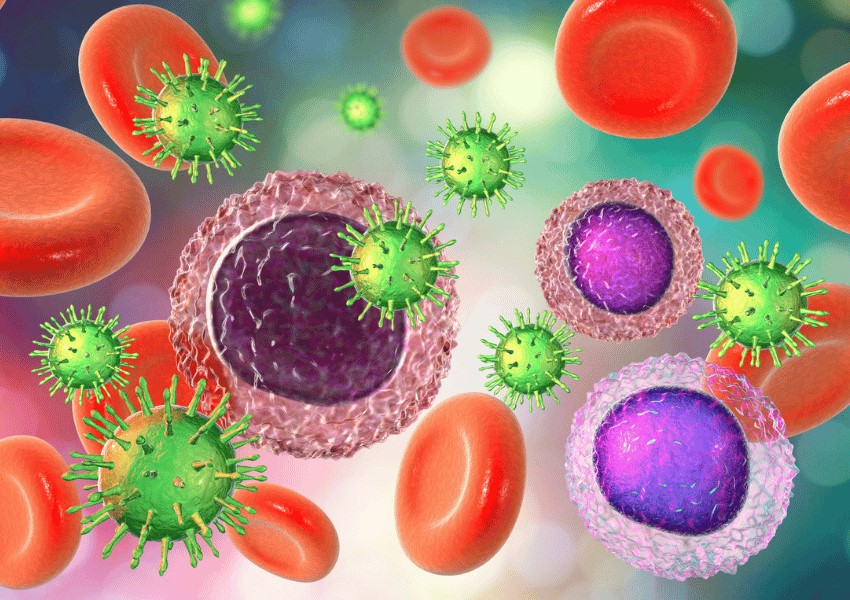

El tratamiento del sistema inmunológico está orientado a fortalecer las defensas naturales del cuerpo, ayudando a prevenir infecciones y a mejorar la capacidad del organismo para responder de manera adecuada ante bacterias, virus y otros agentes externos.

- Infecciones frecuentes o recurrentes.

- Defensas bajas confirmadas por exámenes médicos.

- Refuerza las defensas del organismo.

- Ayuda a reducir la frecuencia de enfermedades.